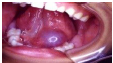

Q.219. Name a condition, shown in the picture below ?

Correct Answer : A